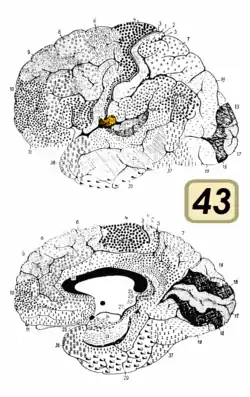

Поле Бродмана 43, субцентральна ділянка, — це структурний, цитоархітектонічно визначений, підрозділ кори великих півкуль головного мозку. Разом з полями Бродмана 1, 2, і 3, Поле Бродмана 43 — це структурний підрозділ постцентральної ділянки мозку.[2] Гістологічна структура цього поля спочатку була описана Корбініаном Бродманом, але на карті кори головного мозку воно не було позначене .[3]

У людському мозку субцентральне поле 43, — це цитоархітектонічно визначений структурний підрозділ постцентральної ділянки кори головного мозку. Воно займає постцентральну звивину, яка знаходиться між вентролатеральним краєм центральної борозни і глибинними ділянками латеральної борозни, в острівцевій корі. Рострально й каудально межує приблизно з передньою субцентральною борозною й задньою субцентральною борозною, відповідно. Цитоархітектонічно поле обмежене рострально aгранулярним лобним полем 6, і каудально, більшою частиною, каудальним постцентральним полем 2 і надкрайовим полем 40[2] .